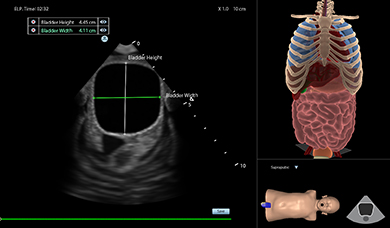

Ultrasound Mentor accelerates the development of basic to advanced technical and cognitive skills, by providing not only the probe manipulation training, but also a didactic environment enabling structured, self-guided learning including step-by-step instructions and educational aids such as 3D anatomical map and probe positioning assistant, all backed up with our progress monitoring tool MentorLearn.

- Advanced diagnostic tools, including Color Doppler, CW, PW, M-mode, and measurements

- Ongoing metrics capturing for accuracy and efficacy measurements including image analysis